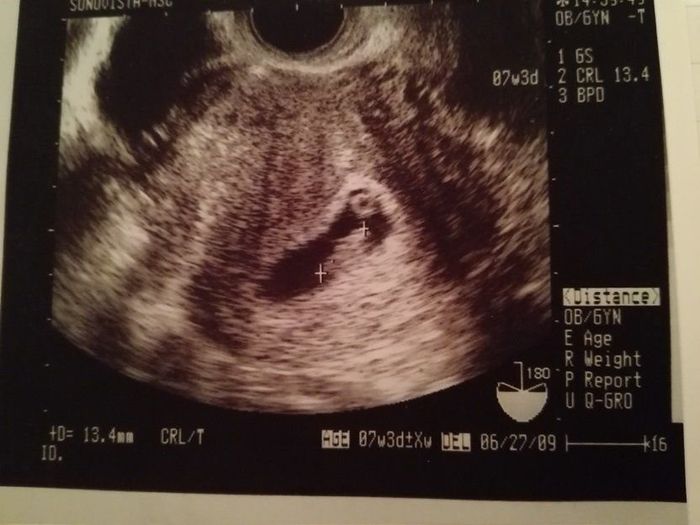

妊娠7週目のエコー写真

画像中央の+と+の間が赤ちゃんで、上の丸い頭のようなものが赤ちゃんに栄養を送る袋(卵黄嚢)だと教えてもらいました。家に帰って、気になっていたエコー写真の記号の意味を調べてみたら以下の通りだと分かり、まだ頭からお尻まで13.4mmなのだとその小ささに驚きました。

GS 胎嚢(たいのう)=胎嚢のサイズ

BPD 児童大横径(じどうだいおうけい)=赤ちゃんの頭の幅。

CRL 頭殿長(とうでんちょう)=赤ちゃんの頭からお尻までの長さ。